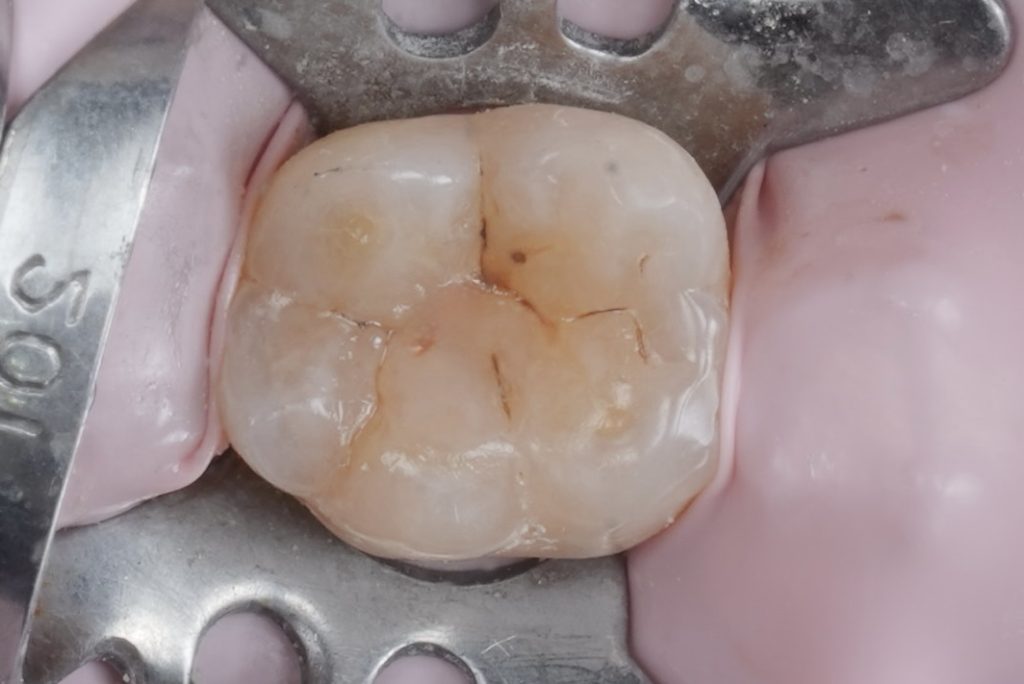

A base layer of Tokuyama Estelite Sigma Quick (A2 shade) was placed in 2 mm oblique increments, each sculpted to mimic natural fissure anatomy. Oblique layering minimized polymerization stress and maximized marginal adaptation (Fig 3).

- Fig 3: Incremental layering of Tokuyama composite.